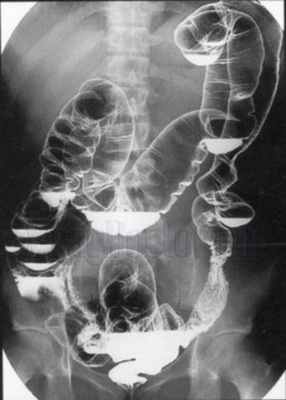

Лучевое исследование толстой кишки. Основным методом исследова-

ния толстой кишки должна быть ирригоскопия – исследование толстой кишки с предварительным введением контрастной взвеси через прямую кишку.

Методика исследования. Контрастная клизма с барием из аппарата Боброва вводится постепенно под контролем экрана, пока контрастная масса не достигнет слепой кишки и не заполнит ее. Под экраном исследуют расправление кишки, размеры, положения петель, состояние контуров, продвижение контрастной массы. Подозрительные участки (изменения) должны фиксироваться на прицельных рентгенограммах. После заполнения всей толстой кишки делается один обзорный снимок на пленке 30 × 40 см, и первый этап исследования считается законченным (рис. 5.15).

Второй этап – исследование рельефа слизистой проводится после опорожнения кишечника (рис. 5.16).

Рис. 5.15. Обзорный снимок брюшной полости при ирригографии (тугое наполнение). Толстая кишка в норме.

Рис. 5.16. Обзорная рентгенограмма брюшной полости. Фаза рельефа в ободочной кишке при ирригографии. Норма.

Под контролем экрана в условиях дозированной компрессии изучаются складки слизистой каждого отдела толстой кишки (прицельные снимки подозрительных участков обязательны). Завершающим методическим приемом является исследование двойным контрастированием, что весьма важно при подозрении на новообразование.

Под контролем экрана проводят раздувание толстой кишки; измененные и подозрительные участки подлежат рентгенографии (прицельные снимки), и последним диагностическим приемом является обзорный снимок на пленке 30 × 40 см всех петель кишечника в состоянии двойного контрастирования (рис. 5.17).

Рис. 5.17. Обзорная рентгенограмма брюшной полости. Двойное контрастирование толстой кишки. Норма.